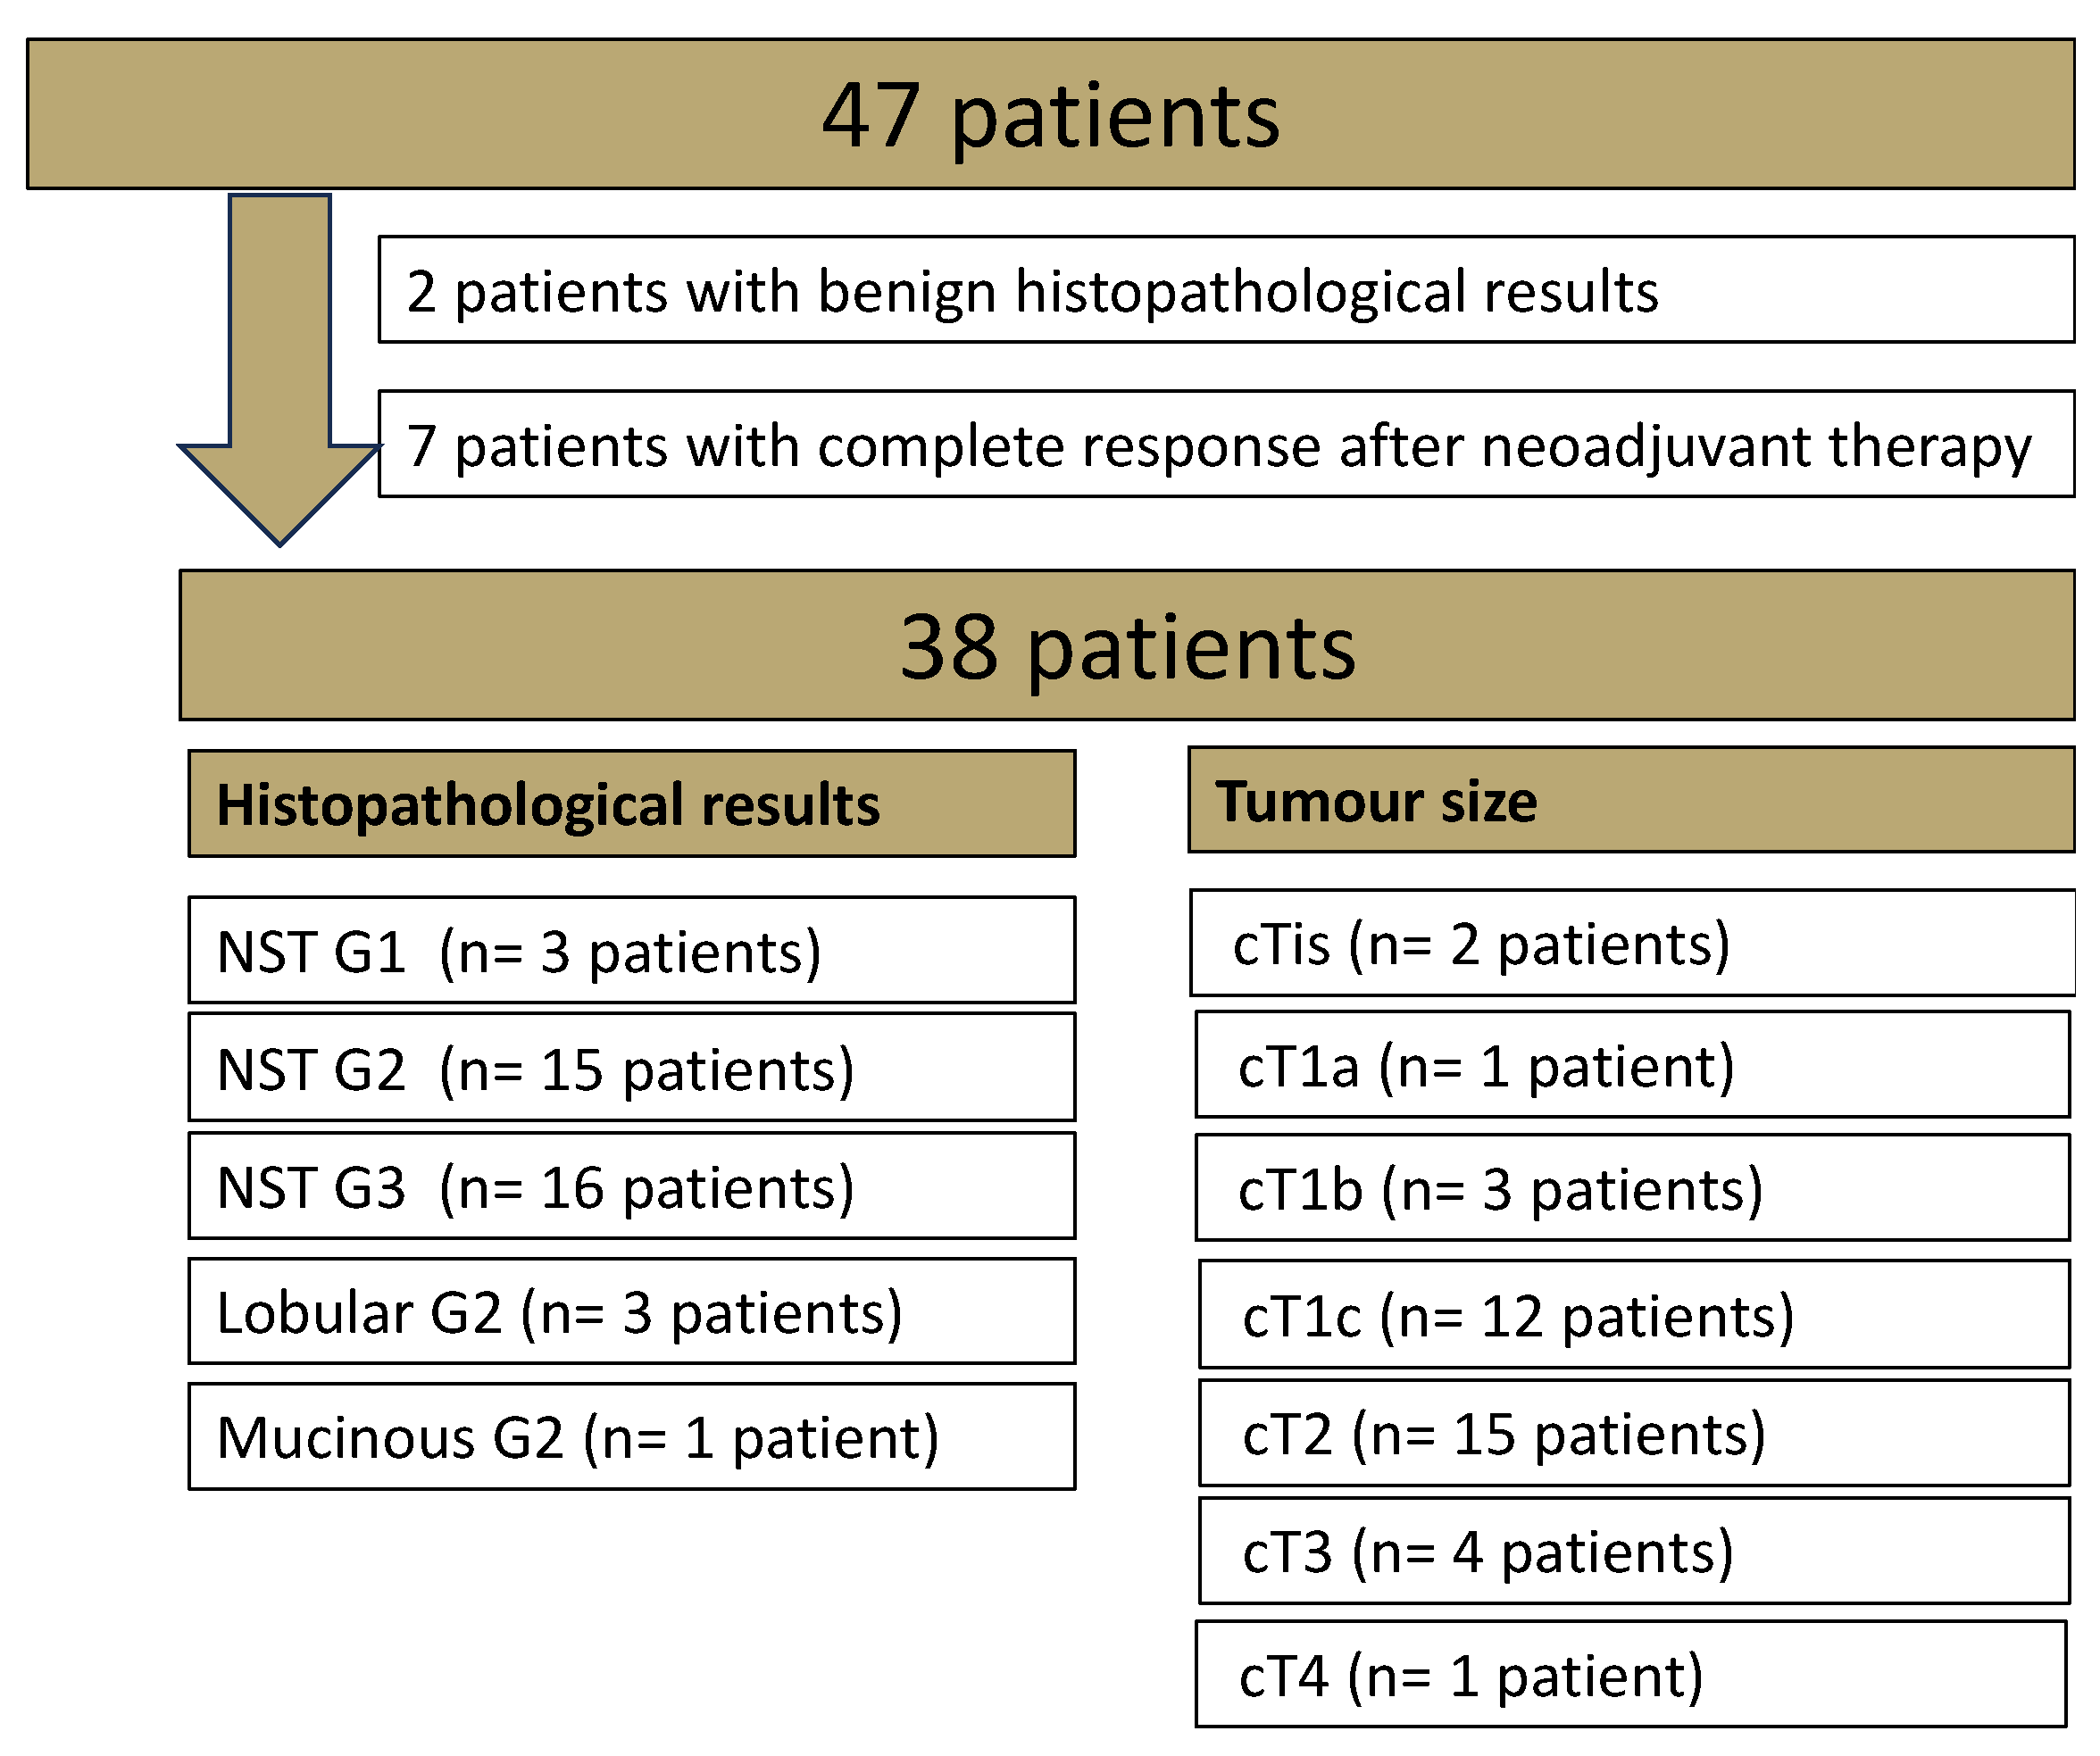

2.1. Patient Cohort

3.1.1. Patients